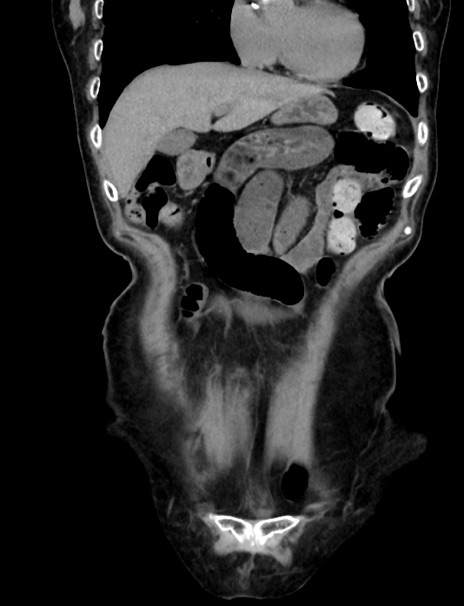

症例33(冠状断像)

【症例】70歳代 女性

【主訴】心窩部痛

【現病歴】延髄病変の精査・加療にて神経内科入院中。本日より心窩部痛あり。

【既往歴】虫垂炎

【身体所見】右下腹部を中心に圧痛と反跳痛あり。

【データ】WBC 10900、CRP 0.02